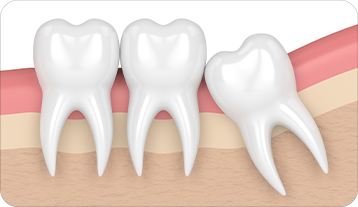

사랑니 발치란 구강 내 가장 뒤 쪽에 위치한 사랑니를

구강질환 예방 또는 해결을 위해 발치하는 것을 말합니다.

사랑니는 입안 깊숙이 위치하여 칫솔모가 잘 닿지 않아 충치와 염증이 잘 생기므로 주기적인 검진이 필요합니다.

사랑니 발치 언제 해야 될까요 ?

옆으로 누워 앞쪽 치아를 미는 경우

단순발치

간단 수술 발치

복잡 수술 발치

뼛속에 있는 사랑니와

그 뼈를

절단하여 발치